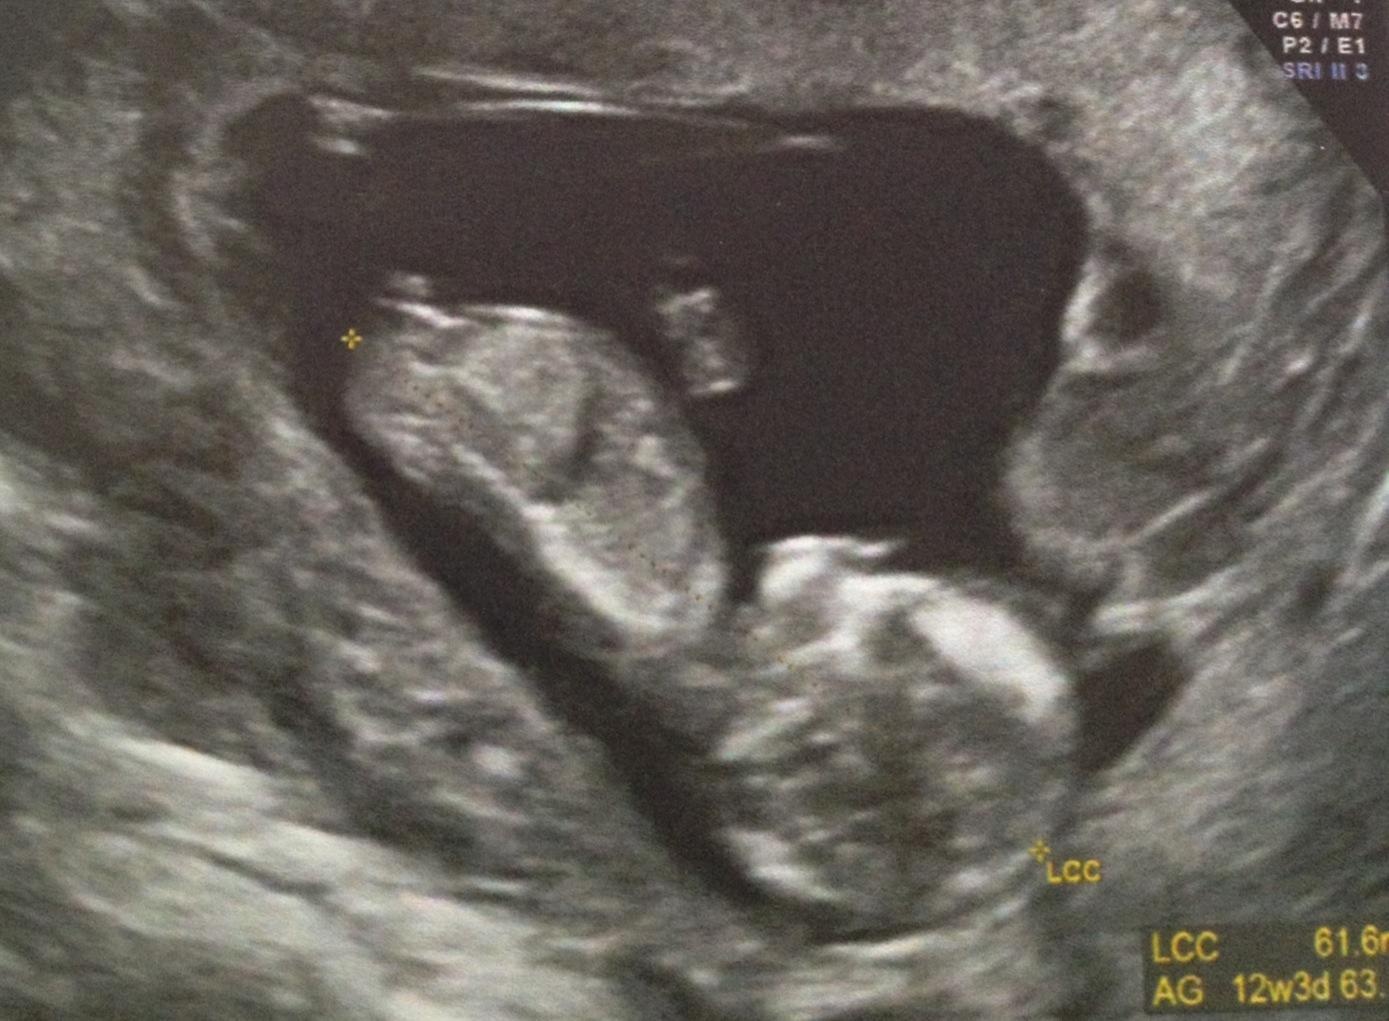

En fait ce que tu as vu Rélie c'est le bourgeon génital! il est le même chez les filles et chez les garçons à ce stade c'est uniquement l'inclinaison par rapport au dos qui permet de dire si c'est un petit mec ou une petite fille... c'est pour ca que certains ne se prononcent pas de suite car des fois le bourgeon n'est pas encore monté par exemple. Mais y a plus de risques d'erreur dans le cas de l'annonce d'une petite fille. Une copine sage femme m'a tout expliqué et elle, ne se prononce pas à cause des risques mais si on t'a dit garçon y a moins d'erreur.Vous pensez que je dois le dire a ma mère et ma belle mère? En fait du coup je flippe un peu lool elle la vu les jambes en l'air donc fesses et sexe juste sous nos yeux et je me dis que si elle été pas sûre elle me l'aurai pas dit non?

Sur cette photo tu vois bien la différence